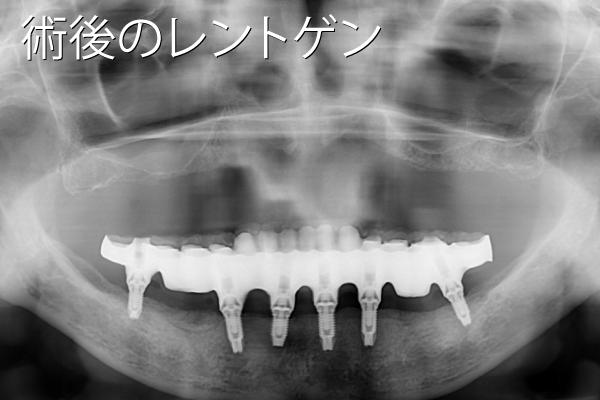

- 性別年齢

- 女性:82歳

- 治療内容

- 下顎にインプラント6本

- 金額

- 385万円(税込)

- 来院理由

- 前歯が抜けそうで噛めなくなってきたので、インプラント治療の相談をしたい。

- 施術の

副作用

(リスク) - 経過とともになくなりますが、術直後に腫れや違和感を感じることがあります。